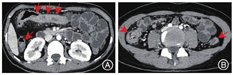

与结肠型CD相比,UC患者的病变更多表现为连续性分布(80%比57.5%,P = 0.03)、肠壁呈环周均匀性增厚(77.5%比47.5%,P = 0.006),较少出现肠周炎性渗出(20.0%比67.5%,P<0.001)及肛瘘(10.0%比57.5%,P<0.001),差异均有统计学意义。结肠型CD病变肠壁厚度大于UC患者[(9.5 ± 3.4) mm比(8.1 ± 2.2) mm,P = 0.024],更多表现为不同部位的严重程度不一致(75.0%比45.0%,P = 0.006),差异均有统计学意义,见图1,图2,图3,图4。两组患者其余影像学特征差异无统计学意义(P均>0.05)。见表3。

根据ROC曲线,将肠壁厚度截取最大Youden指数,其临界值为11 mm,转换为二分类变量分析。上述差异具有统计学意义的影像学变量纳入二元Logistic回归模型中,模型显示升结肠受累(OR = 9.209,95%CI:2.238 ~ 37.902,P = 0.002)、肠周炎性渗出(OR = 9.861,95%CI:2.384 ~ 40.786,P = 0.002)、肛瘘(OR=19.263,95%CI:3.714 ~ 99.905,P<0.001)可作为诊断结肠型CD的有效预测因子,见表4。

与UC相比,结肠型CD更多表现为病变节段性分布、非对称性肠壁增厚,厚度多厚于UC,肠周炎性渗出及肛瘘也更加常见,多变量回归模型也提示肠周炎性渗出、肛瘘是诊断结肠型CD的有效预测因子。多节段性病变是CD的典型影像学表现,而UC患者更多表现为病变连续性分布,与既往报道的一致[15]。另外,结肠型CD患者以非对称性肠壁增厚为主,提示即使位于同一部位的病变,CD患者仍具有跳跃性的趋势,从而表现为影像学上单一节段的肠壁厚薄不均匀。这同样解释了结肠型CD患者在不同部位表现为炎症反应程度不一致的可能原因,而UC患者则更常出现结肠病变相一致的影像学表现。然而,进一步多因素回归分析显示,节段性病变与非对称病变并不能作为诊断结肠型CD的独立预测因子。在肠壁厚度上,结肠型CD患者厚于UC患者,我们认为这与CD表现为累及肠壁全层的透壁性炎症相关,除黏膜层受累之外,黏膜下层炎性水肿也常常同时出现,更有甚者累及肌层之外。而UC仅累及肠壁的黏膜层,病变浸润深度往往表浅,造成了两者影像学上的厚度差异,虽然多因素回归模型显示肠壁增厚没有显著差异(P = 0.051),但肠壁厚度越大,诊断结肠型CD仍具一定的优势比。Ellrichmann等[16]通过超声内镜比较UC与CD的结肠病变厚度,证实了CD黏膜下层厚度高于UC(P = 0.0001),CD平均肠壁厚度稍高于UC,但两者之间差异无统计学意义(P = 0.06)。本研究中,结肠型CD常伴有肠周炎性渗出,而UC患者少见,这或许依赖于两者在病理上累及肠壁的深度及层次有所不同,从而导致继发肠周炎性渗出改变的差异。肠周炎性渗出的出现明显提高了诊断结肠型CD的价值,这也是多因素回归模型中诊断结肠型CD的重要预测因子。另外,结肠型CD患者有50%以上会合并肛瘘,而UC少见,肛瘘是本研究中回归模型的关键预测因子,具有高优势比,其中的具体机制尚不明确,但肛瘘的出现对结肠型CD的诊断具有重要的参考价值。这也提示我们,IBD患者在行腹部检查时,放射医师应尽量覆盖肛管的扫描,这将进一步有助于临床诊断。